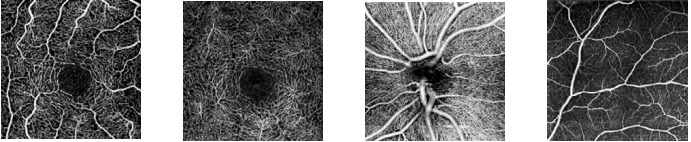

Ангиография SOCT

Является безопасной технологией без применения красителя, с ее помощью можно сделать видимым микроциркуляторное русло сетчатки глаза. Течение крови и полноценная визуализация предоставляют важные недостающие сведения для обнаружения болезней сетчатки. Сканированные изображения ангиографии помогают исследованиям сосудистой сети макулы, периферии и оптического диска. Эта процедура производится за очень маленький промежуток времени – 1,6 секунды при разрешающей способности "стандарт" или приблизительно 3 секунды при разрешающей способности "высокая".